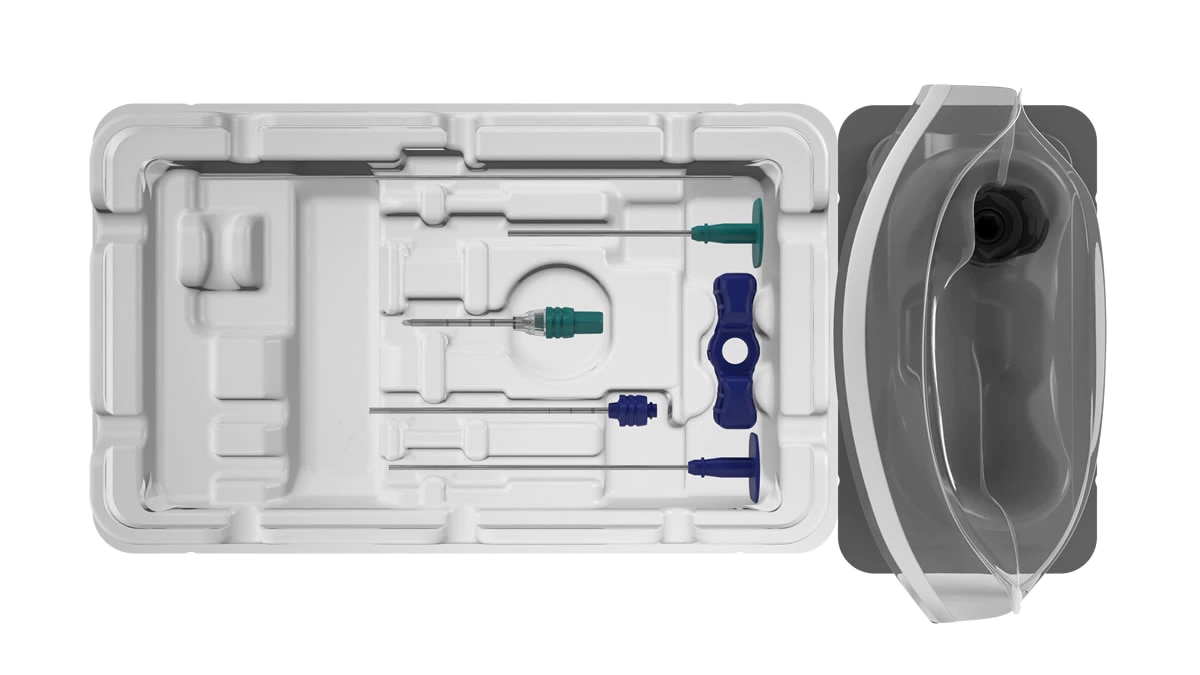

The BD Trek™ Bone Lesion Biopsy System (BD Trek™ Power Driver, BD Trek™ Bone Lesion Biopsy Kit) is intended for bone biopsy of the vertebral body and bone lesions.

The BD Trek™ Bone Lesion Biopsy System (BD Trek™ Power Driver, BD Trek™ Bone Lesion Biopsy Kit) is intended for bone marrow aspiration and biopsy.

Please note that the BD Trek™ Lesion Biopsy Kit is for use in adult patients.

1. Use only BD Trek™ Biopsy Kits with the BD Trek™ Power Driver.